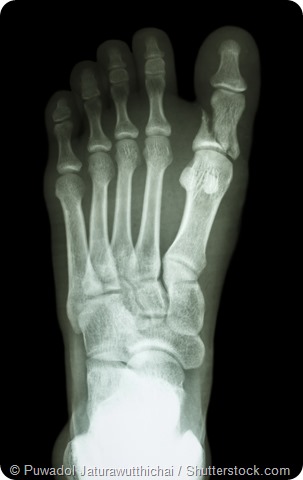

X-ray showing fracture of proximal phalange at first toe

- Fractures: broken or cracked bones in the feet can be very painful.